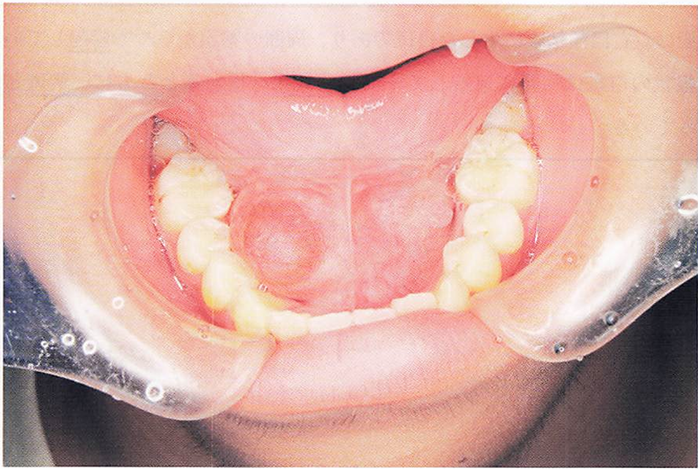

54識の女性。下顎左側の咀噛困難を主訴として来院した。インプラントを 埋入し、上部構造を製作した。製作物の写真と装着時の口腔内写真(ミラー像)を別に示す。 製作物の特徴はどれか。2つ選べ。

a.セメントで合着する。

b.患者が取り外しできる。

c.スクリュー固定である。

d.アクセスホールが存在する。

解答を見る

c.d